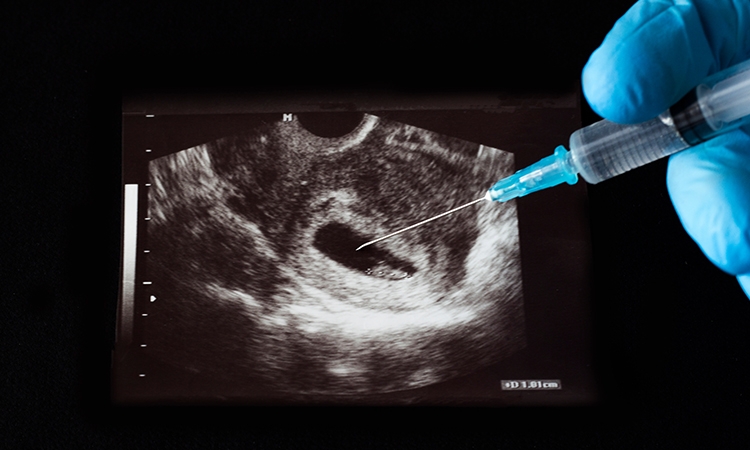

La defensa de los derechos humanos inicia con defender cualquier vida: abortar es matar. Porque defensores de la vida ante los homicidios hay muchos, pero en general evaden el caso del aborto.

¿De qué se trata? De la presión antivida para dar absoluta impunidad a quienes asesinen a una persona nonata. Del aborto, pues, término escondido tras la expresión más cómoda de “interrupción (legal) del embarazo”. Este lenguaje logra convencer a muchos de que se trata de ayudar a una mujer en problemas, lo de como dicen en broma “estar ligeramente embarazada”. Pero es algo que no es ninguna broma, se trata del peor crimen que la sociedad puede avalar, permitir, licenciar, liberar de responsabilidades, darle impunidad legal.

Pero mientras se utilice lenguaje que oculta lo que realmente es, muchas personas pensarán que está bien eso de permitir a las mujeres, impunemente, deshacerse de su hijo nonato, por medio del aborto. Y este término, aborto, también es fácil, desgraciadamente, de aceptar sin condiciones, pues permite a las mujeres, como se busca justificarlo, a vivir su vida sin el problema de cargar con un hijo no deseado (provenga de sexo impuesto o deseado).

Lo que insisto es que el lenguaje permite a los promotores del aborto, convencer a otras personas de que es razonable el despenalizar este delito. Aunque insistan en que realmente es delito, pero que no sea punible, bajo diversas condiciones, como el no haber cumplido cierto número de semanas de embarazo, y aun llegando al terrible grado de que se valga abortar un bebé al término del mismo, justo al dar a luz. Lo más grave es que se defienda la idea de despenalizar el dar muerte a un bebé inmediatamente después del parto. Y esto ya es algo que ni siquiera pueden llamar aborto.

Y abortar es, sin forma de evadirlo, matar una persona nonata (quienes todavía dicen que no es persona, sino una bola de células o algo así tienen la batalla perdida ante la ciencia médica). Y si en vez de hablar de aborto (y menos aún de “interrupción del embarazo”), se usa el lenguaje exacto, que es matar personas nonatas, es más fácil recurrir a la legítima defensa de los derechos humanos, en especial al derecho humano primigenio, el de la vida, sea de nonatos o nacidos.

Si alegamos que la defensa de los derechos humanos inicia con defender cualquier vida, vamos directo al grano: abortar es matar. Porque defensores de la vida ante los homicidios hay muchos, pero en general evaden el caso del aborto.

Quienes alegan que ante un preocupante aumento de asesinatos de mujeres (por ser mujeres) que se debe defender la vida, con la frase conocida de “ni una más”, o la otra de “ni una menos” (viva), deben enfrentar el hecho de que, de cada 100 bebés asesinados en el vientre materno, 49 son mujeres. Y peor aún cuando el aborto “selectivo” se realiza porque el bebé es mujer, se le está matando precisamente por ser mujeres: feminicidios, pues.

Ante las preocupaciones públicas por la inseguridad reinante, que permite que se asesinen personas impunemente, en especial mujeres y menores de edad (allí sí van los varoncitos), se debe incluir la defensa de las personas nonatas, que no se cometan crímenes en su contra impunemente, al incluir en legislaciones penales, que el delito de llámenle aborto, interrupción del embarazo o algo semejante, la liberación de responsabilidad penal. Si se lucha contra la impunidad, tenemos el derecho a exigir que el crimen de matar nonatos no puede gozar de impunidad.